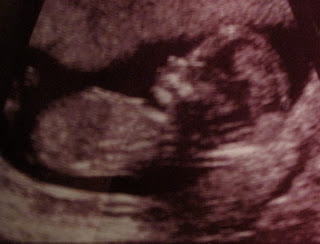

It was amazing to see an ACTUAL looking baby moving around (last time, it looked like a blob).

Well, I was always warned that I would be paid back one day for my, lets just say, ridiculous behaviors as a child. Well, the first 'behavior' appeared on the screen today...the baby was sucking his/her THUMB. Oh dear! It was the most precious sight you have ever seen. I cannot believe a 14 week old baby can find it's mouth and begin the AWFUL (cute) habit of sucking his/her thumb. We were laughing so hard that the ultrasound monitor was bopping all around. Luke and I couldn't believe that it's legs were kicking and it's arm was moving back and forth. We even saw it's mouth open and close. SO COOL! Technology can really bring some amazing moments to life!

He (I keep calling it a him)/SHE was busy, so here are the best pictures the tech could get:

Luke has decided that the baby "totally" has his nose. I'll go with that, he has a nice nose!

Waving "hello"..

I'm kind of cute for being only 14 weeks old..